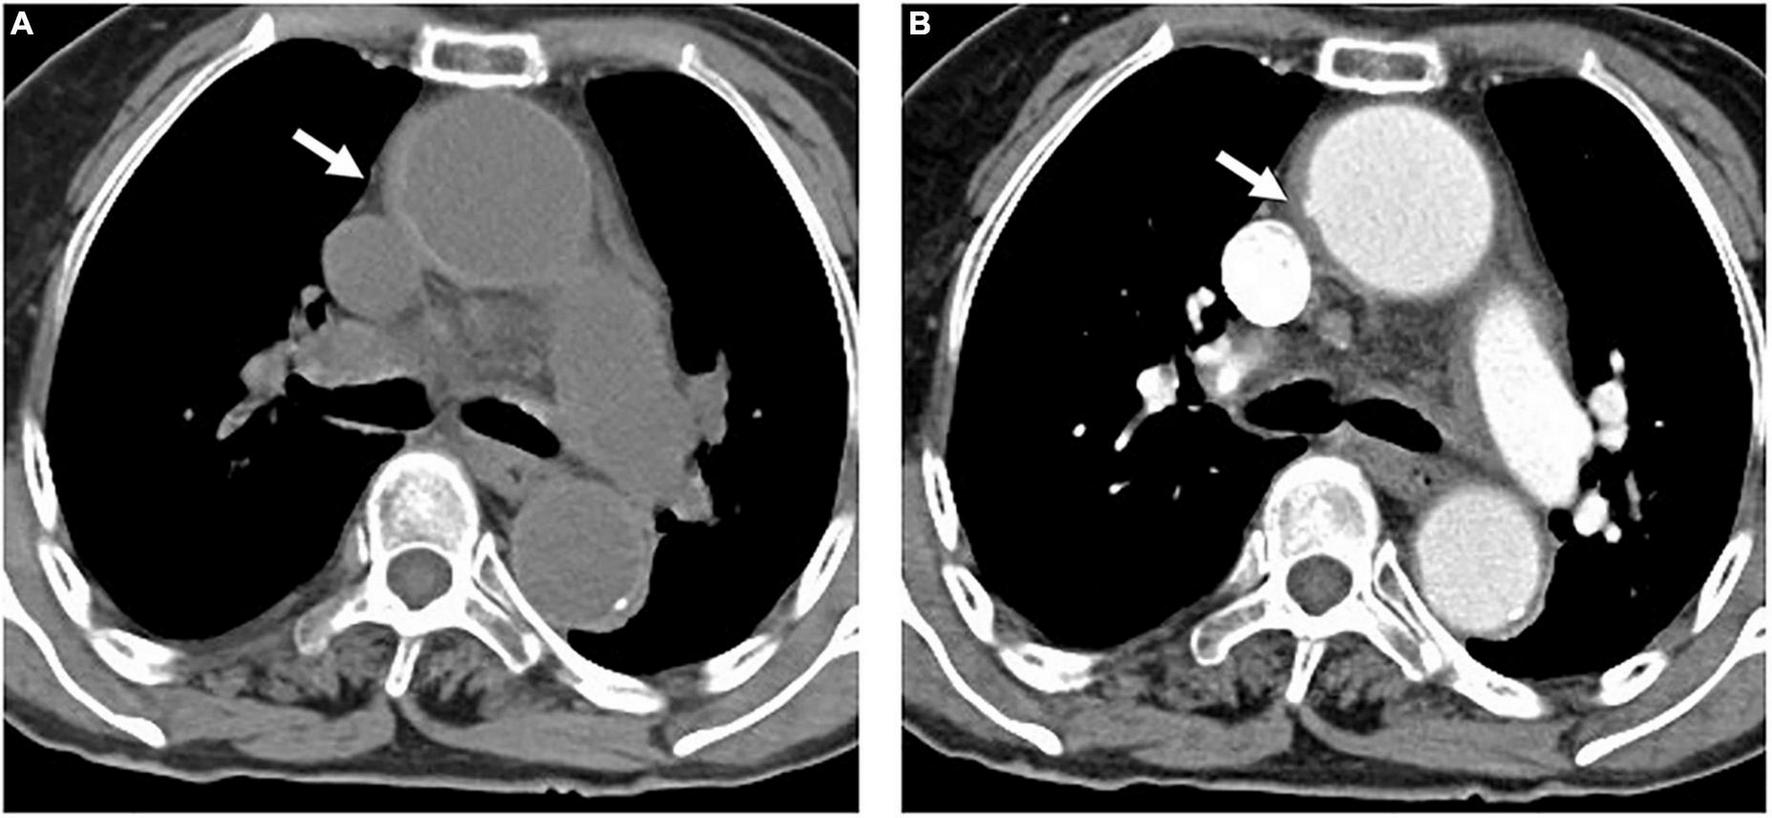

FIGURE 1

An 84-year-old woman with TAIMH and tiny ULP. A precontrast CT scan showed circular high attenuation aortic wall thickening (5 mm) (arrow) involving the ascending aorta (49 mm) (A). A tiny ULP (arrow) was observed in the greater curvature of the ascending aorta (B). Follow-up CT was not performed and the patient suffered from sudden death on the fourth day of admission. CT, computerized tomography; TAIMH, type A aortic intramural hematoma; ULP, ulcer-like projection.